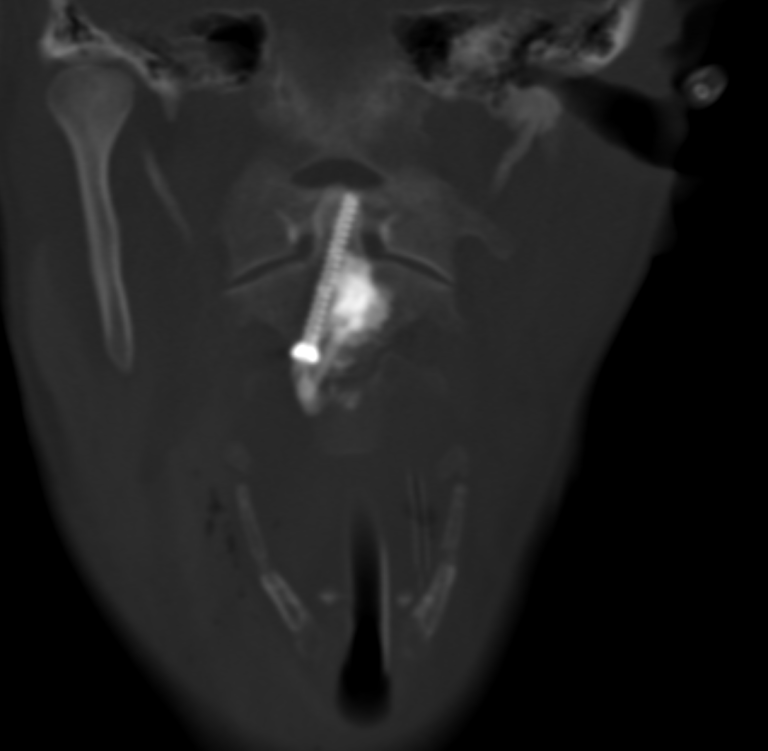

L’ostéosynthèse de la dent de C2 par voie percutanée latéro-cervicale est une technique innovante, peu répandue en France et non réalisée jusqu’alors en Auvergne. Elle a été démocratisée par des équipes lyonnaises et parisiennes, et se distingue par son efficacité clinique et un faible taux de complications.

L’intervention se déroule en salle de radiologie interventionnelle, sous anesthésie générale. Grâce à un guidage scanner et scopique en continu, une précision millimétrique est assurée à chaque étape :

• Hydrodissection cervicale : injection de sérum physiologique pour écarter les structures à risque (artère carotide, veine jugulaire, trachée).

• Mise en place de la vis : introduction d’un trocart osseux, puis d’une broche et enfin d’une vis canulée adaptée à l’anatomie du patient.

• Cimentoplastie complémentaire : injection de ciment acrylique dans la lésion pour renforcer la consolidation et la stabilité de la vis.

Quelques images de l'intervention...